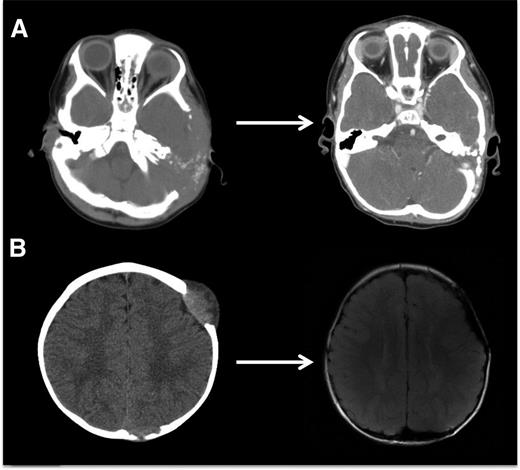

PET scan is effective in evaluating response to treatment of most lesions (Figure 4) except vertebral lesions, which may be better visualized by MRI that will capture changes in soft tissue or enhancement of the bone.28 Vertebral CT scans may add information on bone response to therapy and CT scans are also optimal for following bony lesions of the skull, whereas MRI is most effective for parenchymal brain and pituitary lesions. Bone healing may lag resolution of other lesions (Figures 5-6). CT scanning is also an optimal study to evaluate lung lesions, though cysts may remain as permanent consequences following resolution of nodular parenchymal lung lesions (Figure 7). Clinical examination is sufficient follow-up for proven skin-limited disease, and patients with single bone lesions may be followed by clinical examination, radiograph, or MRI to minimize radiation exposure.

LCH bone lesions may remodel if margins remain intact. These cases highlight the potential for even very large bone lesions to remodel following disease resolution. (A) Skull CT scans before and after chemotherapy in a patient with multifocal bone LCH. Remodeling following systemic chemotherapy nearly normalizes bone structure in a patient with significant skull lesions. This patient did not have any curettage or excisional surgery in the skull. (B) Brain MRI in a patient with multifocal bone LCH before and after complete excision with placement of mesh grafts. Complete excision of LCH lesion with margins into healthy bone inhibits potential for remodeling. Following resections and successful chemotherapy, skull defects persist.